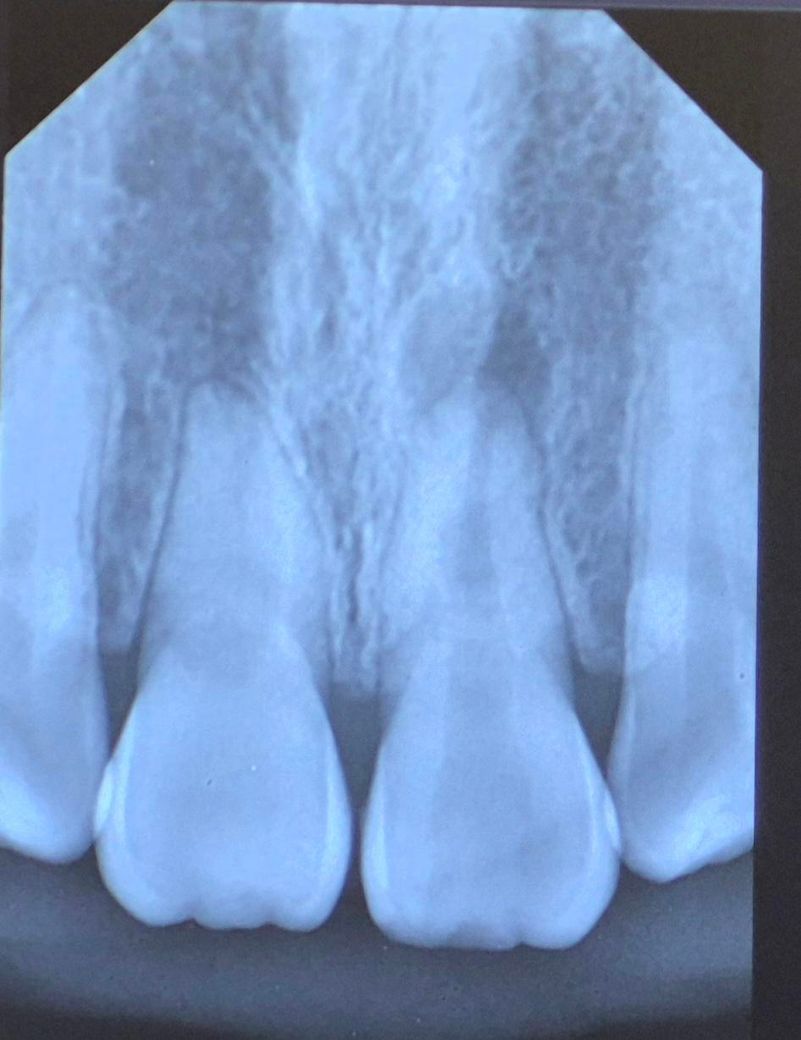

얼마전 치아를 세게 부딪혀서 병원에 갔더니 신경이 손상 됐다고 하셨습니다. 사진상으로 봤을 때 어떤상태인지 설명해주시면 감사하겠습니다.

본인 기준 왼쪽의 치아 끝에 검게 보이는게 염증으로 보여지고 신경치료가 필요한것으로 보입니다. 빠른 회복바라겠습니다. 건강하세요.

오른쪽 위 앞니의 뿌리 끝 염증이 잡혀있는게 보입니다 저건 꼭 외상 때문이었다기보단 예전부터 치근단염증이 잡혀있었을것 같습니다 단기간내에 생기진 않아요